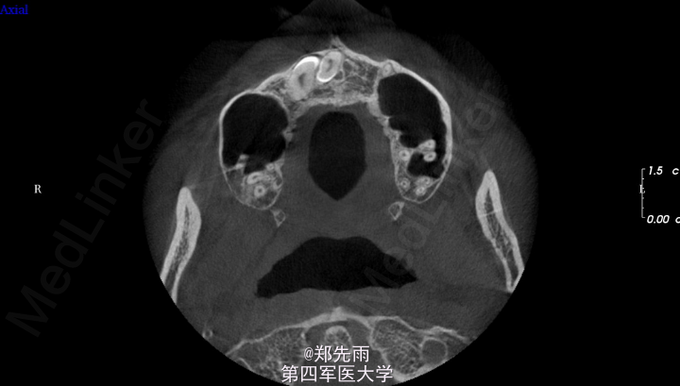

正畸要求拔除埋伏牙转诊。 正畸要求拔除上前牙区埋伏13、多生牙以及24、34、44、18、28、38.

13先天性埋伏阻生,前鼻棘下方埋伏牙,行CBCT检查提示均位于唇侧,但CBCT提示双侧上颌后牙牙根不同程度位于上颌窦内。

诊断:13埋伏阻生,上颌埋伏多生牙。 处理:住院拔除上颌埋伏牙,分次拔除正畸减数牙。与患者术前充分沟通上颌窦穿孔、上颌窦瘘的可能。